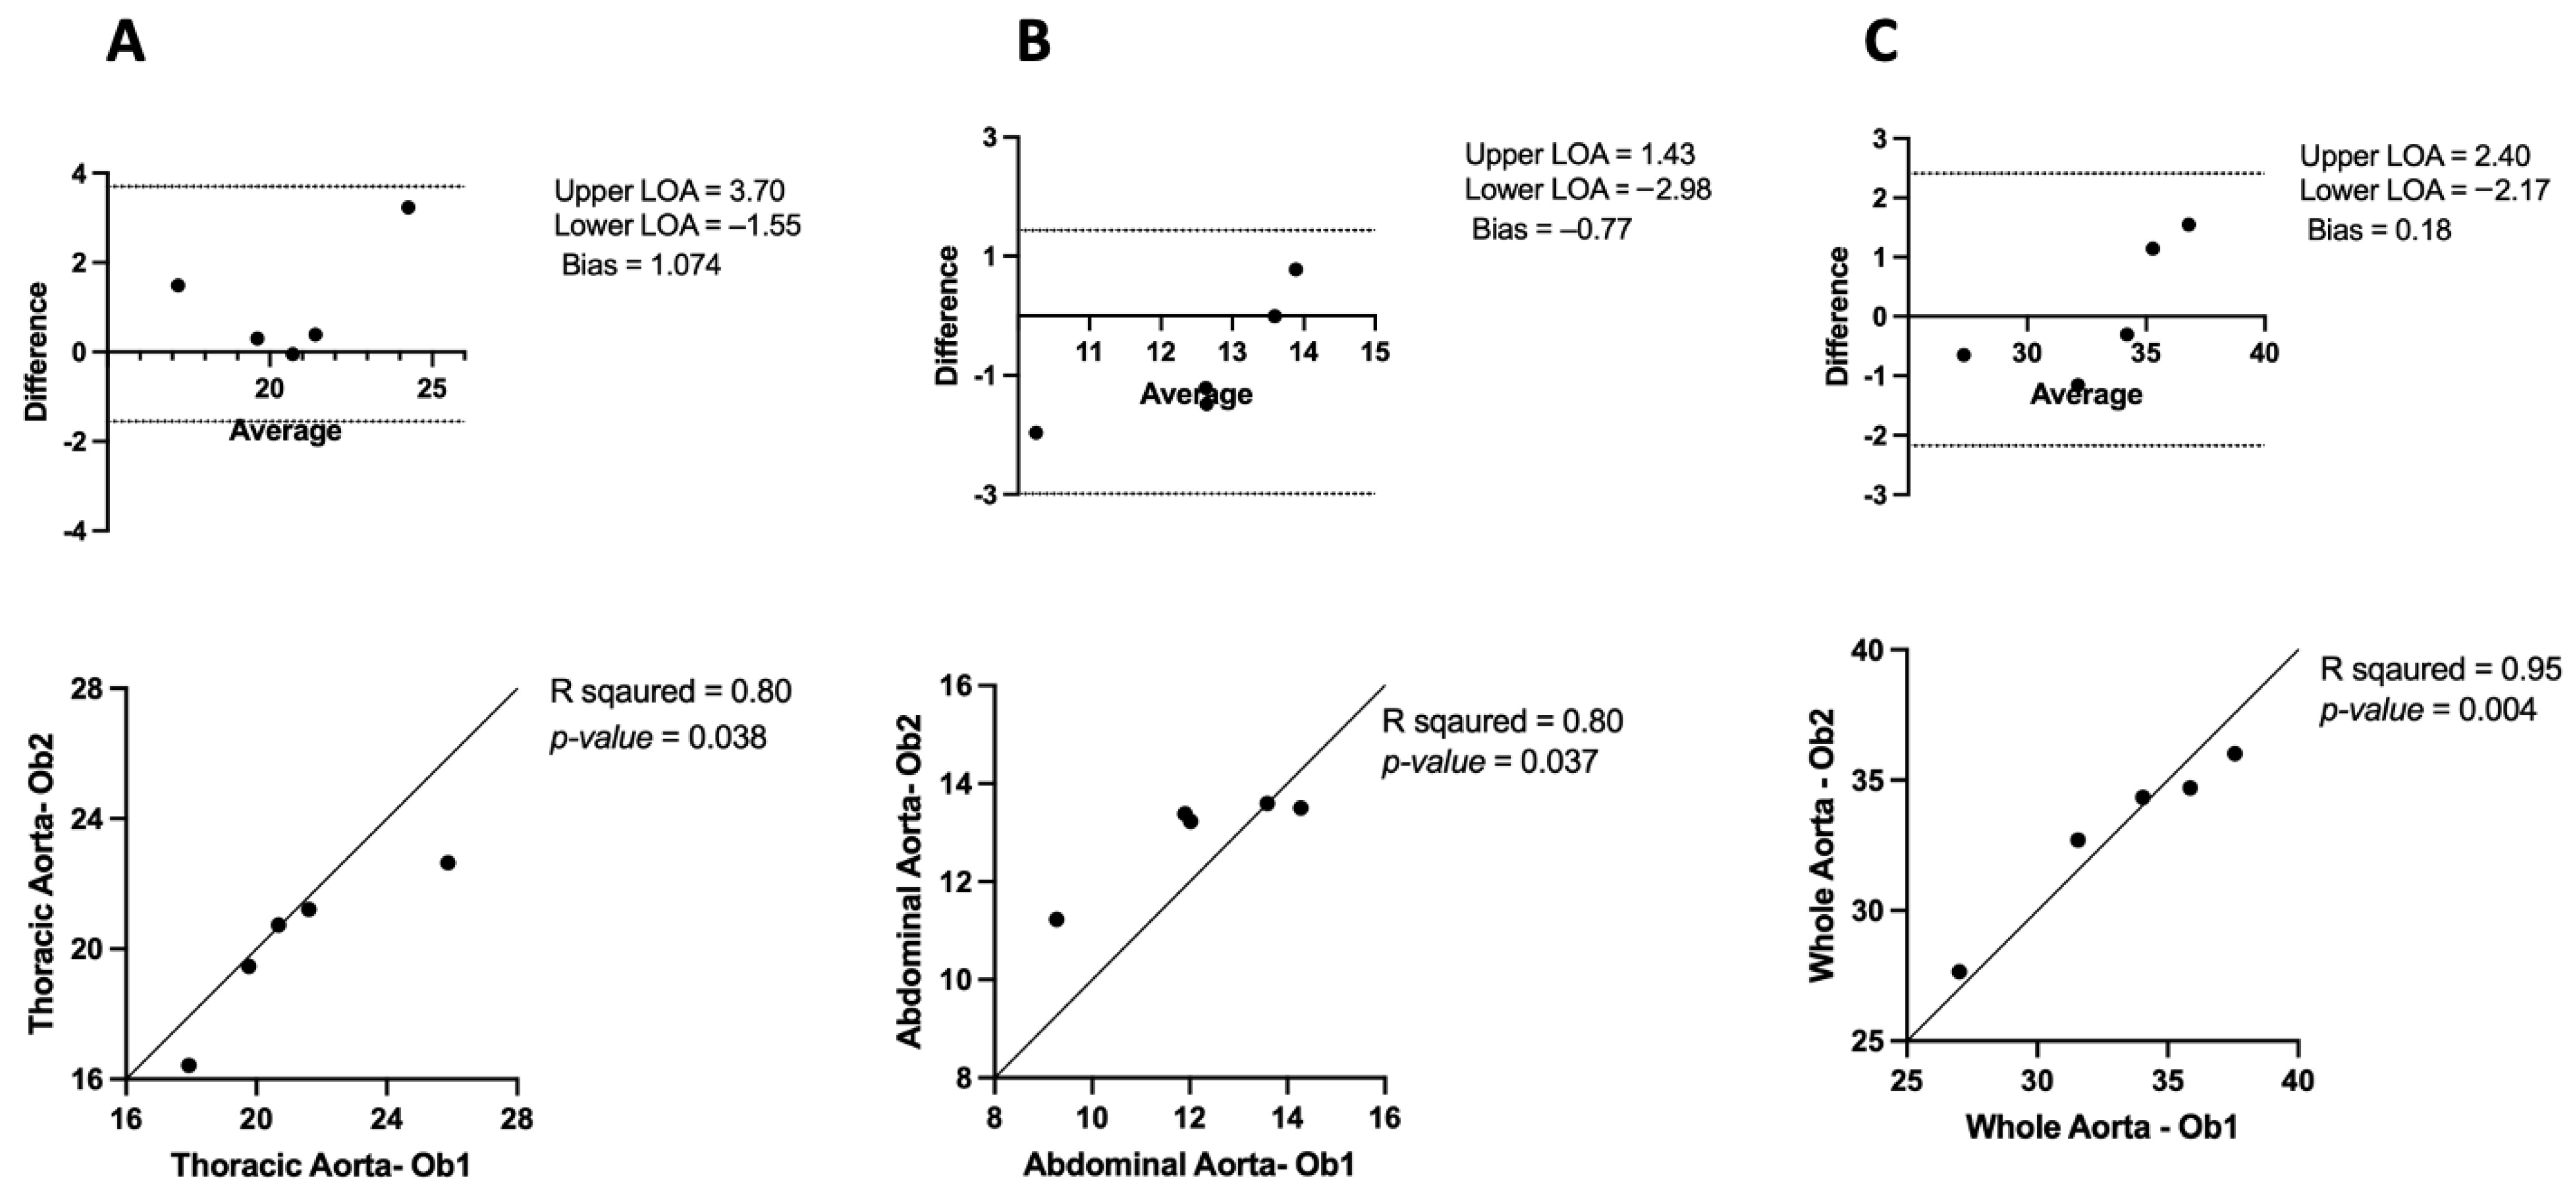

3.1. Inter-Observer and Intra-Observer Variability in μCT

3.1.2. Intra-Observer Variability

4.1. Inter- and Intra-Observer Variability